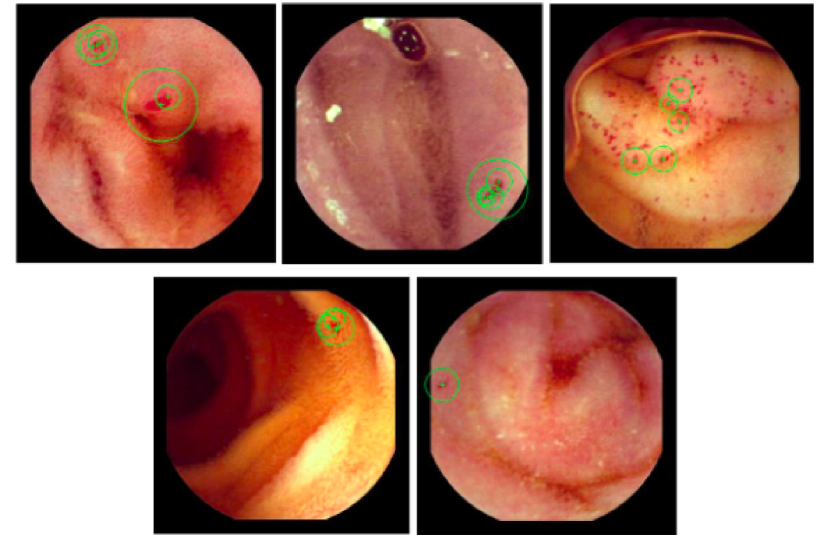

Thus, the interest points detected using SURF algorithm on the ‘a’ component of the CIELab colour space can be represented as the centre of the circular areas as shown in Fig (4).

Refer to caption

Figure 4: Interest points selected using SURF on ‘a’ component